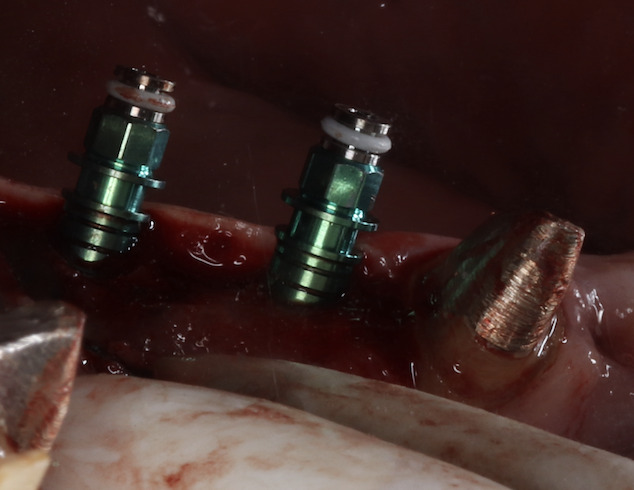

先日、インプラントのオペを行いました。骨が不十分なところに、ソケットリフトという骨造成のテクニックを併用してインプラントを2本埋入しました。

患者様曰く、以前に他院でインプラントができないと言われたそうですが、骨造成を併用すれば問題なくインプラントのオペができました。

上顎は鼻と近いため、骨が不十分なケースがあります。その場合、鼻と交通している上顎洞という空洞に骨造成してインプラントを埋入します。ソケットリフトは上顎洞に骨造成するテクニックの一つです。骨造成の中では、比較的侵襲の少ないテクニックです。